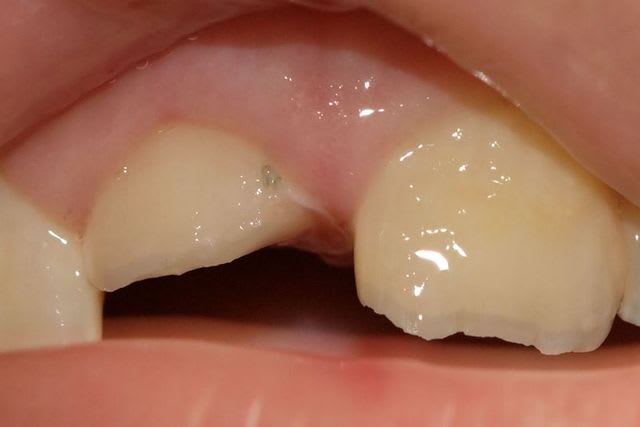

Regardez ce que je viens de recevoir de mon prothésiste habituel.

Vous conviendrez que le résultat n'est pas terrible, mais est assez représentatif de ce que je reçois.

A chaque fois, je met en cause mes piètres talents de prise de teinte, mais vous constaterez sur la deuxième photo que j'étais quand même plus proche que lui.

Le teintier que je présente est un A3,5.

sans même avoir vu la teinte choisie , au vu de la photo c'est ce que j'aurai choisi

et effectivement on est pas loin du B1 surtout en saturation de blanc du fait de l'opacité caractérisée

c'est du monocouche flagrant